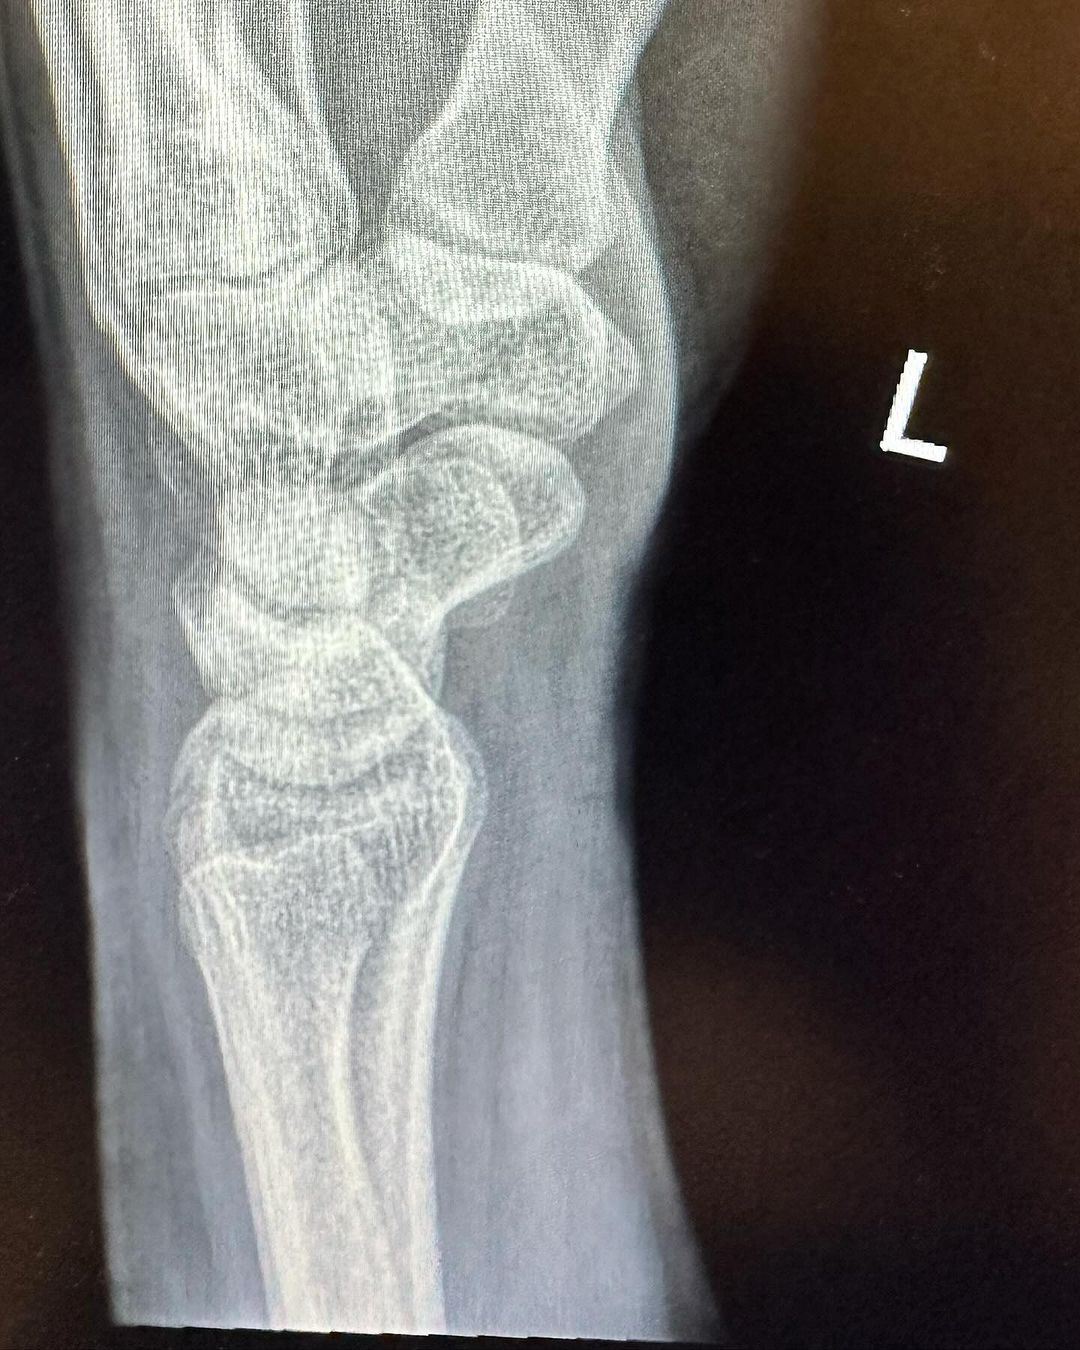

Pelakon, Azira Shafinaz berkongsi berita duka apabila tulang pergelangan tangannya mengalami keretakan gara-gara terjatuh ketika menjalani penggambaran sebuah drama.

“Alhamdulillah tiada kecederaan serius, cuma retak yang sangat kecil (hairline fracture) bahagian tulang pergelangan tangan. Tolong doakan saya segera pulih,” tulis beliau menerusi hantaran di Instagram.